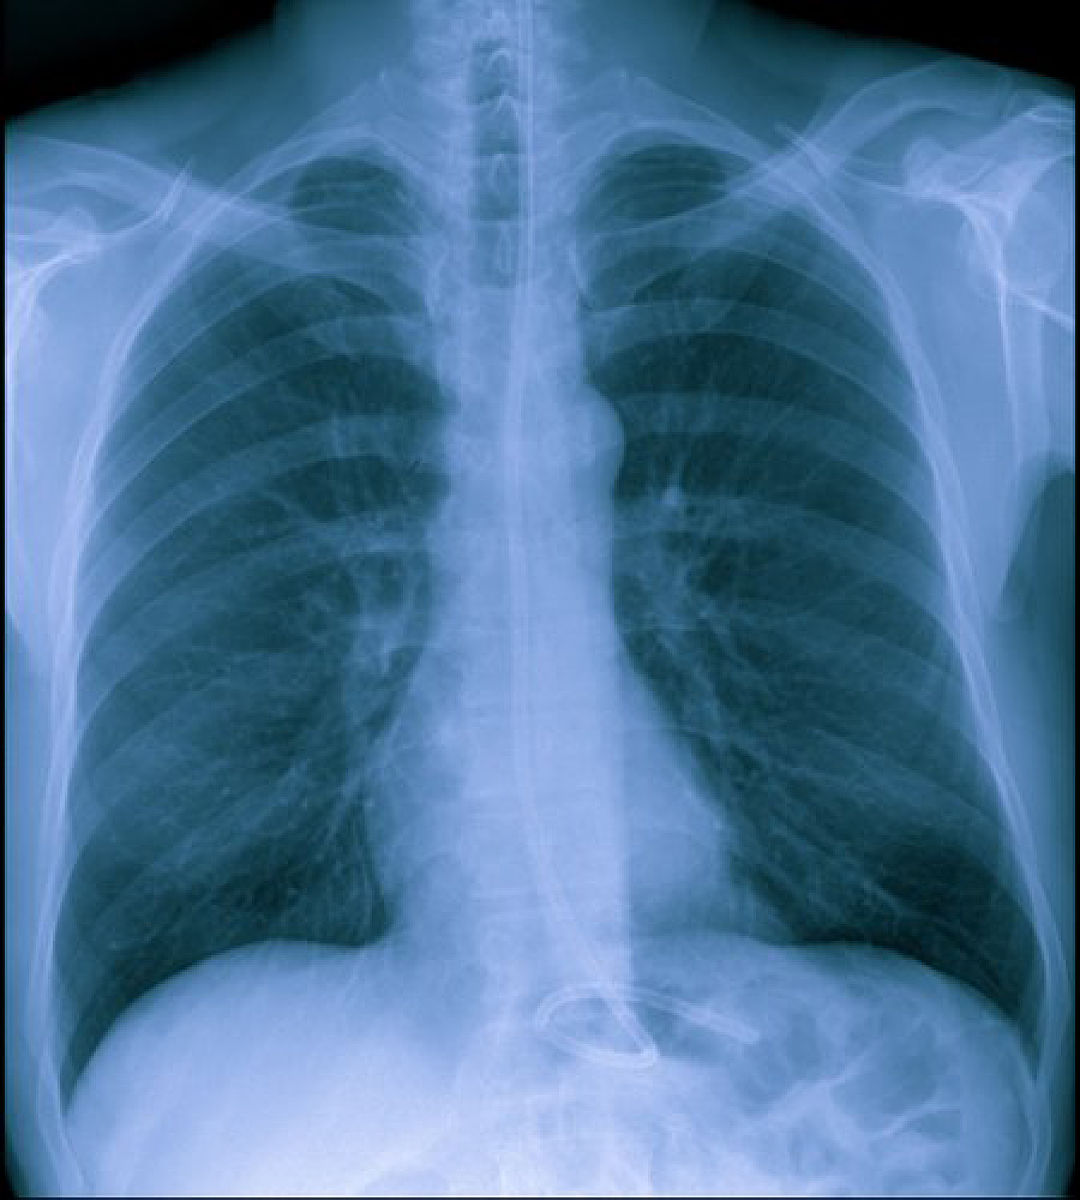

胸部CT检查会产生一定的辐射,但剂量在安全范围内,单次检查的辐射伤害极小,无需过度担心。

CT检查是利用X射线穿透人体成像,会产生电离辐射,胸部CT的辐射剂量约为2-5mSv,而人体每年可接受的安全辐射剂量上限约为50mSv,单次检查的剂量远低于这个标准。